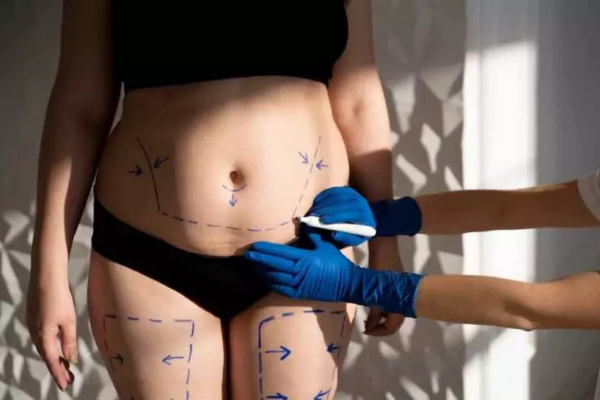

Pós Operatório